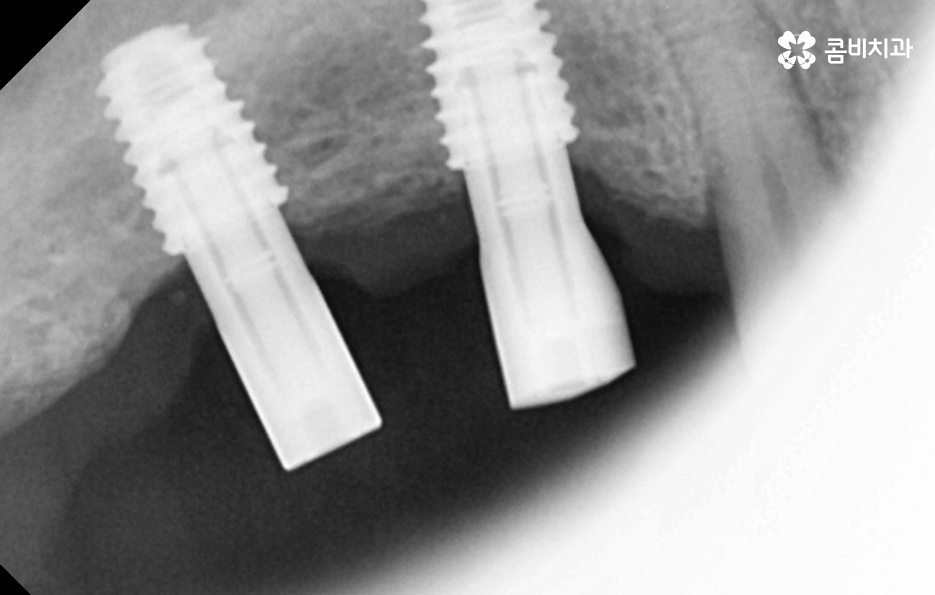

임플란트의 시술 원리는 잇몸 뼈에 식립하게 되기 때문에 충분한 골조직이 없을 때는 시술 성공률도 낮아질 뿐 아니라 장기적인 안정성도 떨어지기 때문에 잇몸 뼈가 부족하신 분들은 뼈이식을 추가적으로 해야할 수 있어요

만약 치주염으로 인해 50대임플란트 해야 하는 분들의 경우에는 뼈이식을 추가적으로 받아야 하는 경우가 있겠고 임플란트의 안정성을 확보하기 위해서는 임플란트를 고정해줄 수 있는 일정한 두께와 식립 깊이, 골질이 건강해야 하는데요

50대는 앞으로의 기대수명이 길기 때문에 치아 상실 후 방치하기 보다는 꼭 임플란트 치료를 하는 것이 합리적이며 치아 상실 후에는 골 흡수가 진행되지만 임플란트를 하면 잇몸 뼈를 보존할 수 있다는 점에서도 앞으로의 노후대비에 있어서도 임플란트는 중요한 시술이 될 수 있어요